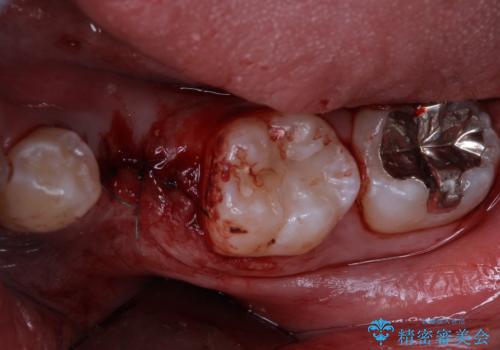

- 乳歯を抜歯したところにインプラントをしたいと来院された患者様です。

永久歯の先天欠如による乳歯の晩期残存があり、その乳歯が虫歯になってしまい保存不可能になり、他院で抜歯をし義歯を使用していた状態です。

義歯では嚙みづらいため、インプラントによる補綴をしていくこととしました。

- 外科手術のため、術後に痛みや腫れ、違和感を伴います

- メンテナンスを怠ったり喫煙により、お口の中に大きな悪影響を及ぼすインプラント周囲炎等にかかる可能性があります